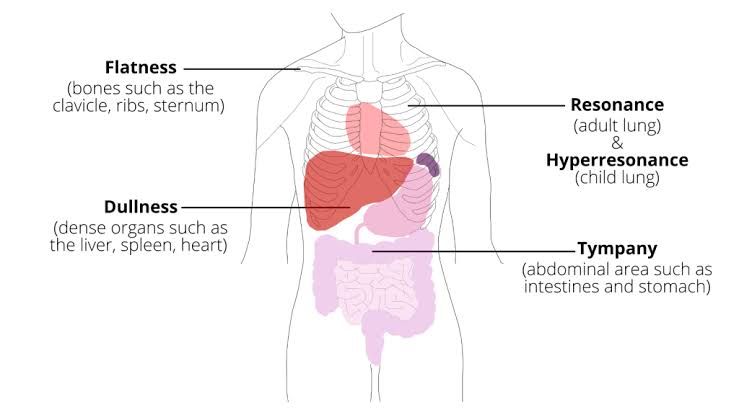

• Resonance sound (રેઝોનન્સ સાઉન્ડ) :

- રેઝોનન્સ એ લો પીચ સાઉન્ડ છે. જે મુખ્યત્વે એરવાળા એરિયામાં સાંભળવાં મળે છે. જેમકે થોરાસિક કેવિટીમાં (Lungs)

• Dull sound (ડલ સાઉન્ડ):

- ફ્લુઇડવાળા એરિયામાં ડલ સાઉન્ડ સાંભળવાં મળે છે. જેમકે હાર્ટ, લીવર, સ્પલીન

• Flat sound (ફ્લેટ સાઉન્ડ):

- સોલિડ એરિયામાં ફ્લેટ સાઉન્ડ સાંભળવા મળે છે.જેમકે બોન, મસલ્સ

• Tympanic સાઉન્ડ (ટિમ્પેનીક સાઉન્ડ):

- ટિમ્પેનીક સાઉન્ડ એ હોલો, ડ્રમ લાઇક સાઉન્ડ છે. જે બ્લોટેડ સ્ટમક વાળા એરિયામાં સાંભળવા મળે છે એટલેકે એર પ્રેસર ધરાવતા એરિયામાં સાંભળવા મળે છે.

Hyperresonance sound (હાઇપરરેઝોનન્સ સાઉન્ડ):

- જ્યારે થોરાસિક કેવિટીમાં વધારે માત્રામાં એર ભરાયેલ હોય ત્યારે હાઇપરરેઝોનન્સ સાઉન્ડ સાંભળવા મળે છે. જેમકે ન્યુમોથોરેક્સની કન્ડીશન

- જ્યારે થોરાસિક કેવિટીમાં ડલ સાઉન્ડ સાંભળવા મળે તો તે થોરાસિક કેવિટીમાં ફ્લુઇડ એકયુમ્યુલેટ થયેલ છે તે ઇન્ડીકેટ કરે છે.